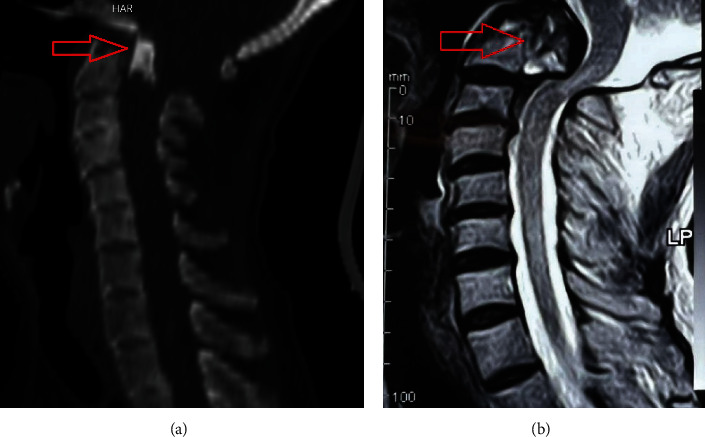

Background: Odontoid fracture (OF) is one of the most common spinal fractures. Type II in D'Alonzo's classification is still the most common and should be considered unstable unless proven otherwise. Thus, surgical stabilization has received significant attention. Although posterior displacement is common in type II OF, complete displacement is extremely rare, and very few reports are available in the literature. Case Presentation: We report the case of a 60-year-old man with acute type II OF with complete posterior displacement and myelopathy. The patient was managed utilizing a posterior-only single approach for reduction and stabilization. Conclusion: Posterior displacement of type II OF has been traditionally managed with close reduction and anterior or posterior stabilization. Closed reduction in cases of complete posterior displacement carries a significant risk of neurologic deterioration. Anterior, combined, and posterior approaches have been taken for this condition. The posterior-only approach in experienced hands has the least mortality and morbidity with at least the same neurologic and fusion outcomes.

Abstract Image